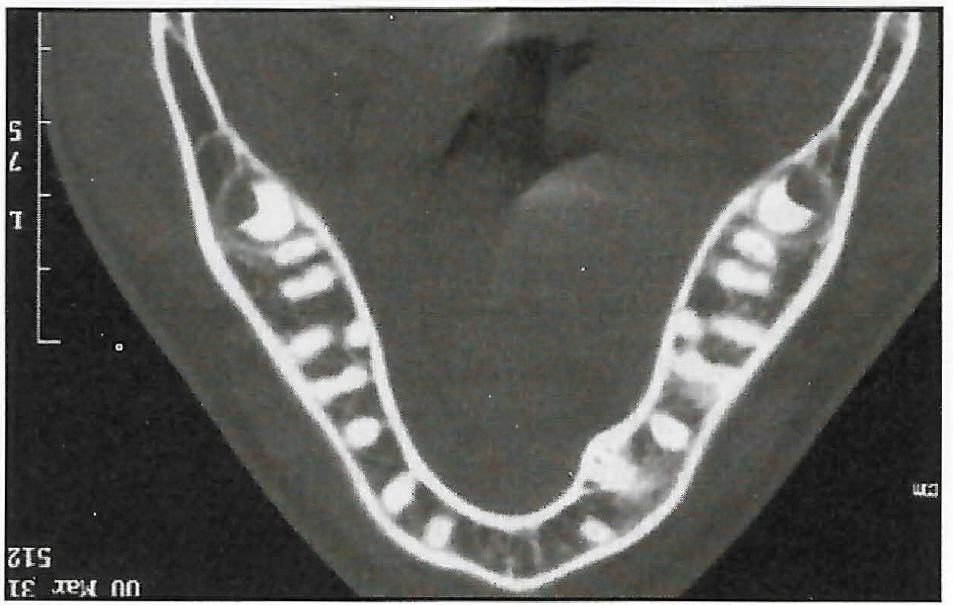

An 11-year-old female presented with a Class II, division 1 malocclusion and severe crowding of the upper and lower anterior segments. The maxillary right and mandibular left permanent canines were unerupted and completely blocked out. The patient had an 8mm overjet and 100% overbite, with the lower incisors occluding on the palate (Fig. 13).

Fig. 13 Case 2. Before treatment.